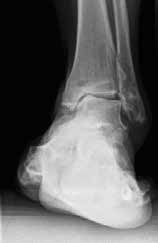

Das besondere Merkmal der Arthrose des OSG ist das relativ junge Alter der Patienten im Vergleich zur Arthrose anderer Gelenke der unteren Extremität, da die meistens zugrunde liegenden Traumata Sportunfälle sind. Zusätzlich werden ein schnellerer Funktionsverlust des Gelenks und eine beschleunigte Progression der Erkrankung bis zum Erreichen des Endstadiums (innerhalb von 10 bis 20 Jahren) beobachtet 9 (Abb. 2a). Negativ beeinflussende Faktoren für die Entwicklung einer Arthrose des OSG sind: Achsfehlstellungen oder angeborene Deformitäten der unteren Extremität, Muskeldysbalance 10, angeborene oder erworbene ligamentäre Fehlentwicklungen, Alter, Geschlecht und genetische Prädisposition 11.

Weiterhin führen Fehlstellungen im Rückfuß zu statischen und dynamischen Überlastungen, da sich bei Varusfehlstellung (Abb. 2a) das Zentrum der Kraftübertragung nach medial und bei Valgusfehlstellungen nach lateral verlagert 47. Die Achillessehne wirkt durch ihren Zug zusätzlich invertierend bei Varusfehlstellung und evertierend bei Valgusfehlstellung auf den Rückfuß ein 48. Möglichkeiten der operativen Therapie sind entweder die einfache Umstellungsosteotomie der distalen Tibia und Fibula als rein supramalleoläre Osteotomie mit dem Ziel einer Überkorrektur des distalen Tibiagelenkflächenwinkels von 3 bis 5° 49 oder die kombinierte Osteotomie an Bein und Rückfuß (Abb. 2b) mit oder ohne Weichteileingriff je nach Topographie der Achsfehlstellung 50. Weitere Möglichkeiten sind die Calcaneusosteotomie, meist als ergänzende Osteotomie nach Wiederherstellung der korrekten Achse (Abb. 2b) im Sinne einer Verschiebeosteotomie, um die Zugrichtung der Achillessehne zu zentrieren, und die Osteotomie der medialen Säule, die bei durch Valgusfehlstellung induzierter Abflachung des medialen Längsgewölbes indiziert sind. Hierbei werden zusätzlich korrigierende Arthrodesen des I. Strahls (Naviculo-cuneiforme-Gelenk, Tarsometatarsalgelenk) oder plantarflektierende Osteotomien (Cuneiforme I oder Metatarsale I) durchgeführt 51.